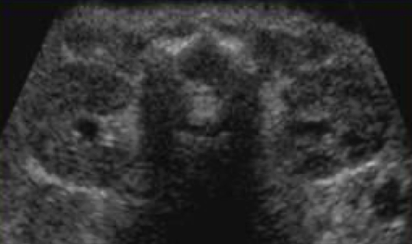

what plane was this taken in?

longitudinal